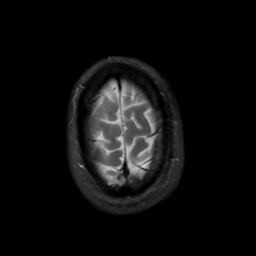

MR Study #2, February 17, 1991 -- Slice #45

[Home][Help][Clinical][Tour 1][Tour 2] Slice 45